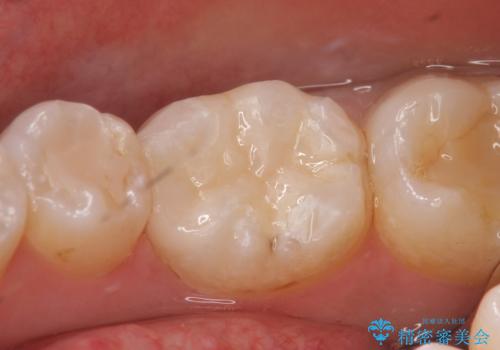

- 銀歯を白くして欲しいといらっしゃった方の症例です。

銀歯及び虫歯を除去後、セラミックインレーによる修復を行いました。

当院のセラミックインレーはemaxという強度と審美性に優れた材料を使用しています。

またプレス方式でインレーを製作しているため、削り出しで製作するCADCAMより優れた適合性も持ち合わせており、虫歯が再発しにくい修復物です。